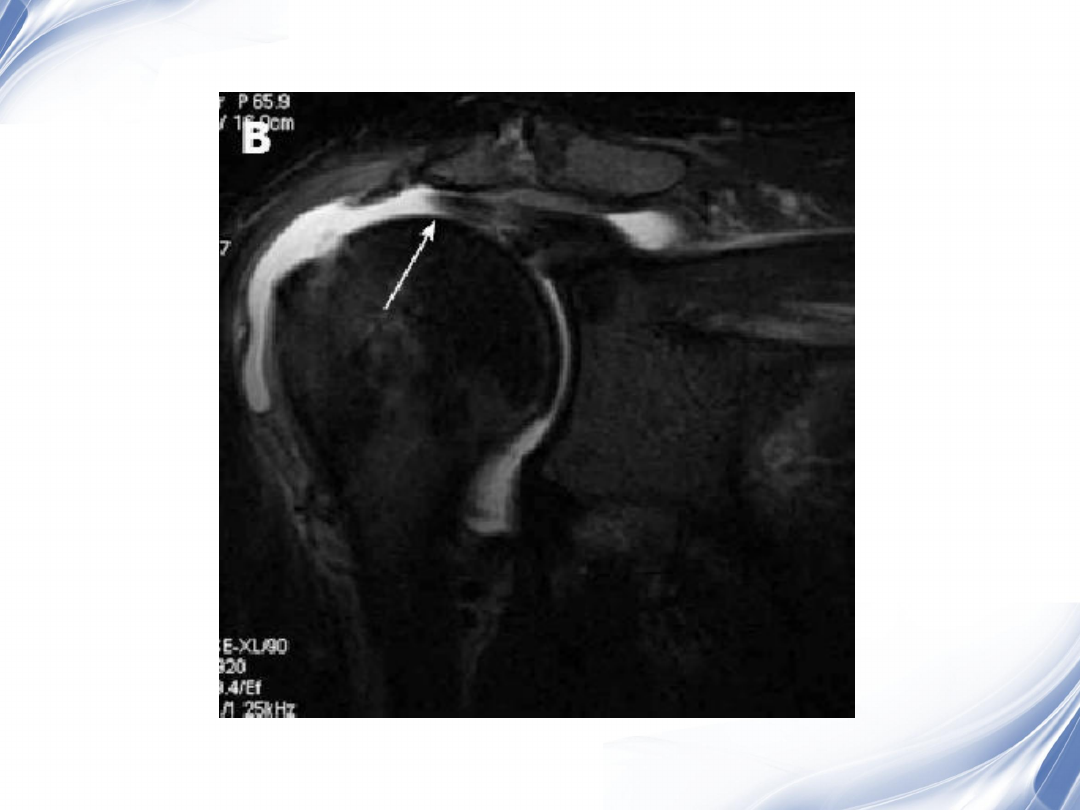

34

肩袖全层撕裂

正常MRI

background image

35